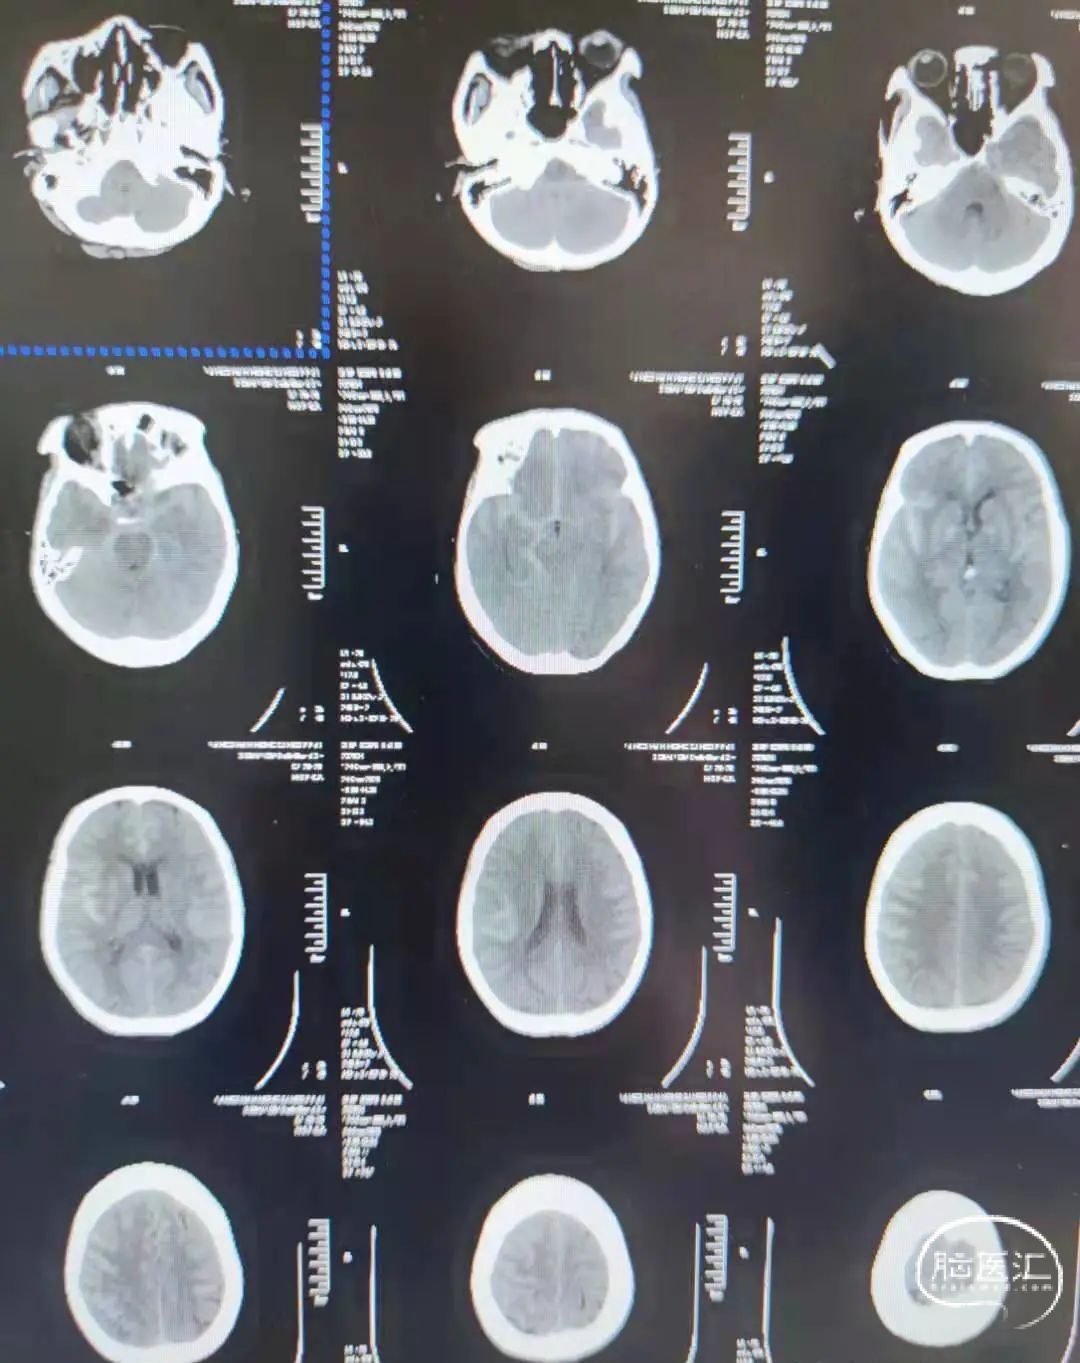

因蛛网膜下腔出血入院,入院Hunt-Hess2级。

术前影像